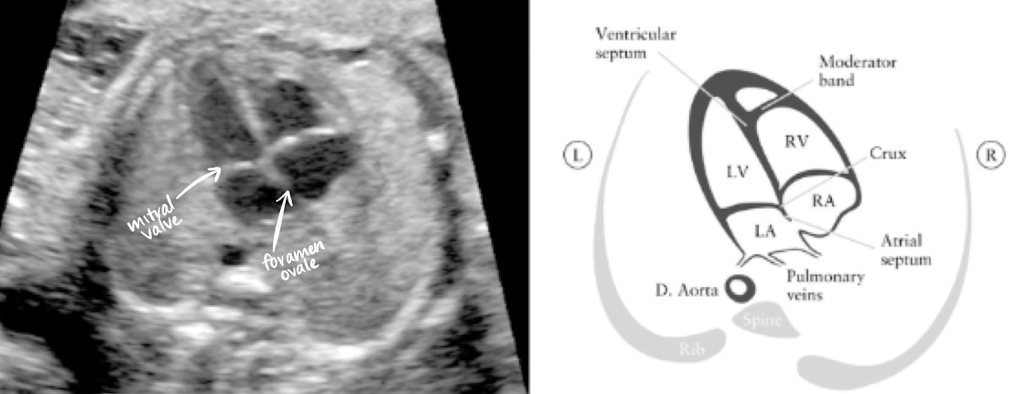

US evaluation of 4-chamber heart

make note of right and left side

lung should be seen on both sides of the heart

ensure no fluid or masses seen adjacent to/around the heart

LA is closest to AO and spine

foramen ovale opens between RA and LA

note symmetry between atria and ventricles

tricuspid valve is on right side (b/w RA and RV)

bicuspid/mitral valve is on left side (b/w LA and LV)

imaging the 4-chamber heart

obtained from TRV view of abdomen just above diaphragm

make sure to have ribs on both sides during 4CH view

must see ribs on both sides to be true TRV rather than oblique

heart takes up 1/3rd of chest

heart angles 45 degrees to the left